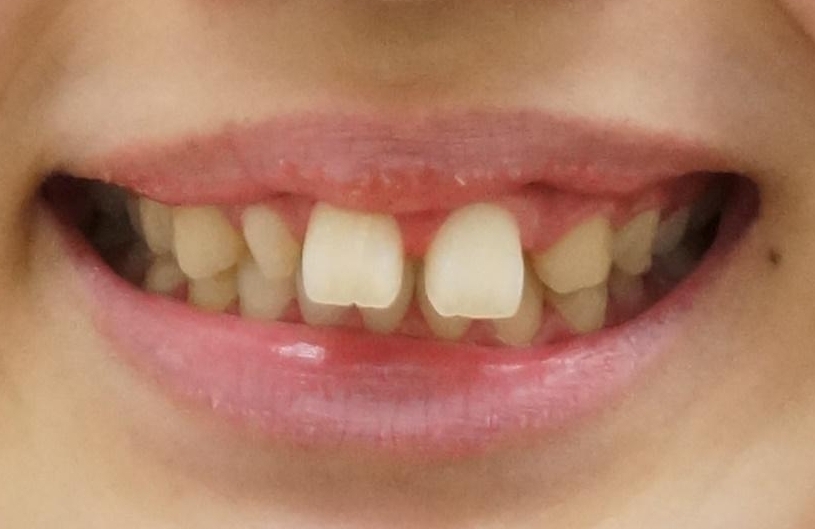

前歯が出っ歯ですきっ歯 抜かずに前歯を見た目良く

- 前歯の並びを主訴に来院。

前歯が出ており、また、左上の側切歯が1本生まれつき少ない状態でした。

また、右の奥歯の関係も上が前にある状態で大きくずれていました。

今回は左右とも1歯対2歯の関係であるため、それは変えずに前歯を可及的にひっこめて足りない部分をブリッジで補う治療としました。

奥歯の関係を完全に1級にするには右上の小臼歯の抜歯が必要でしたが、もともと左上の前歯が生まれつき少ないため今回は歯を抜かずに治療しています。